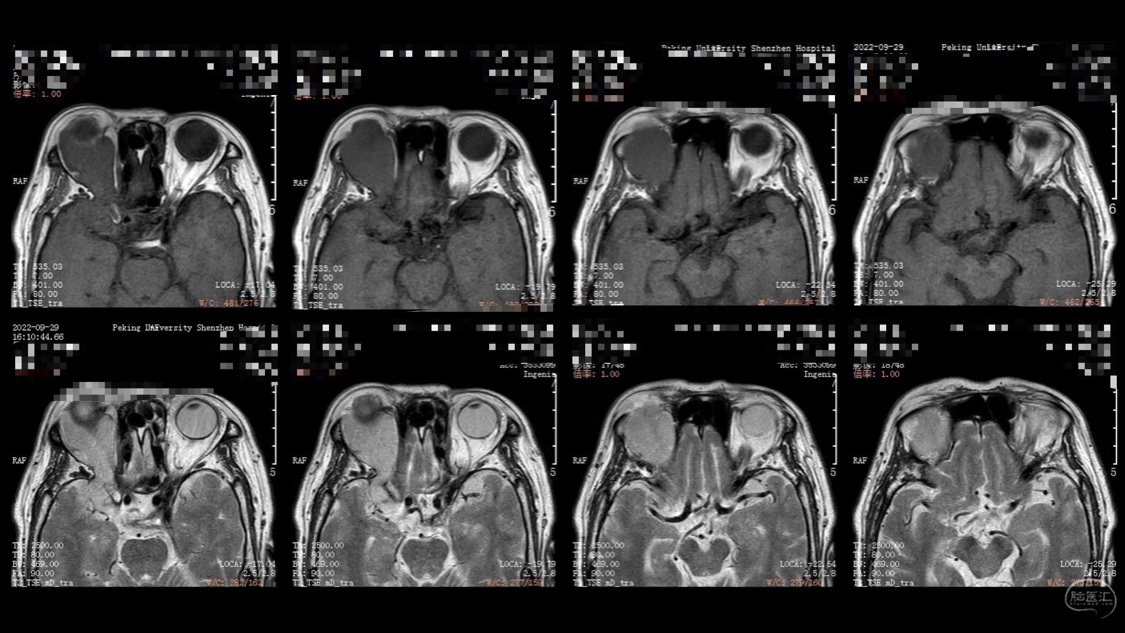

陈保东教授手术作品-右眶内及海绵窦旁孤立性纤维瘤